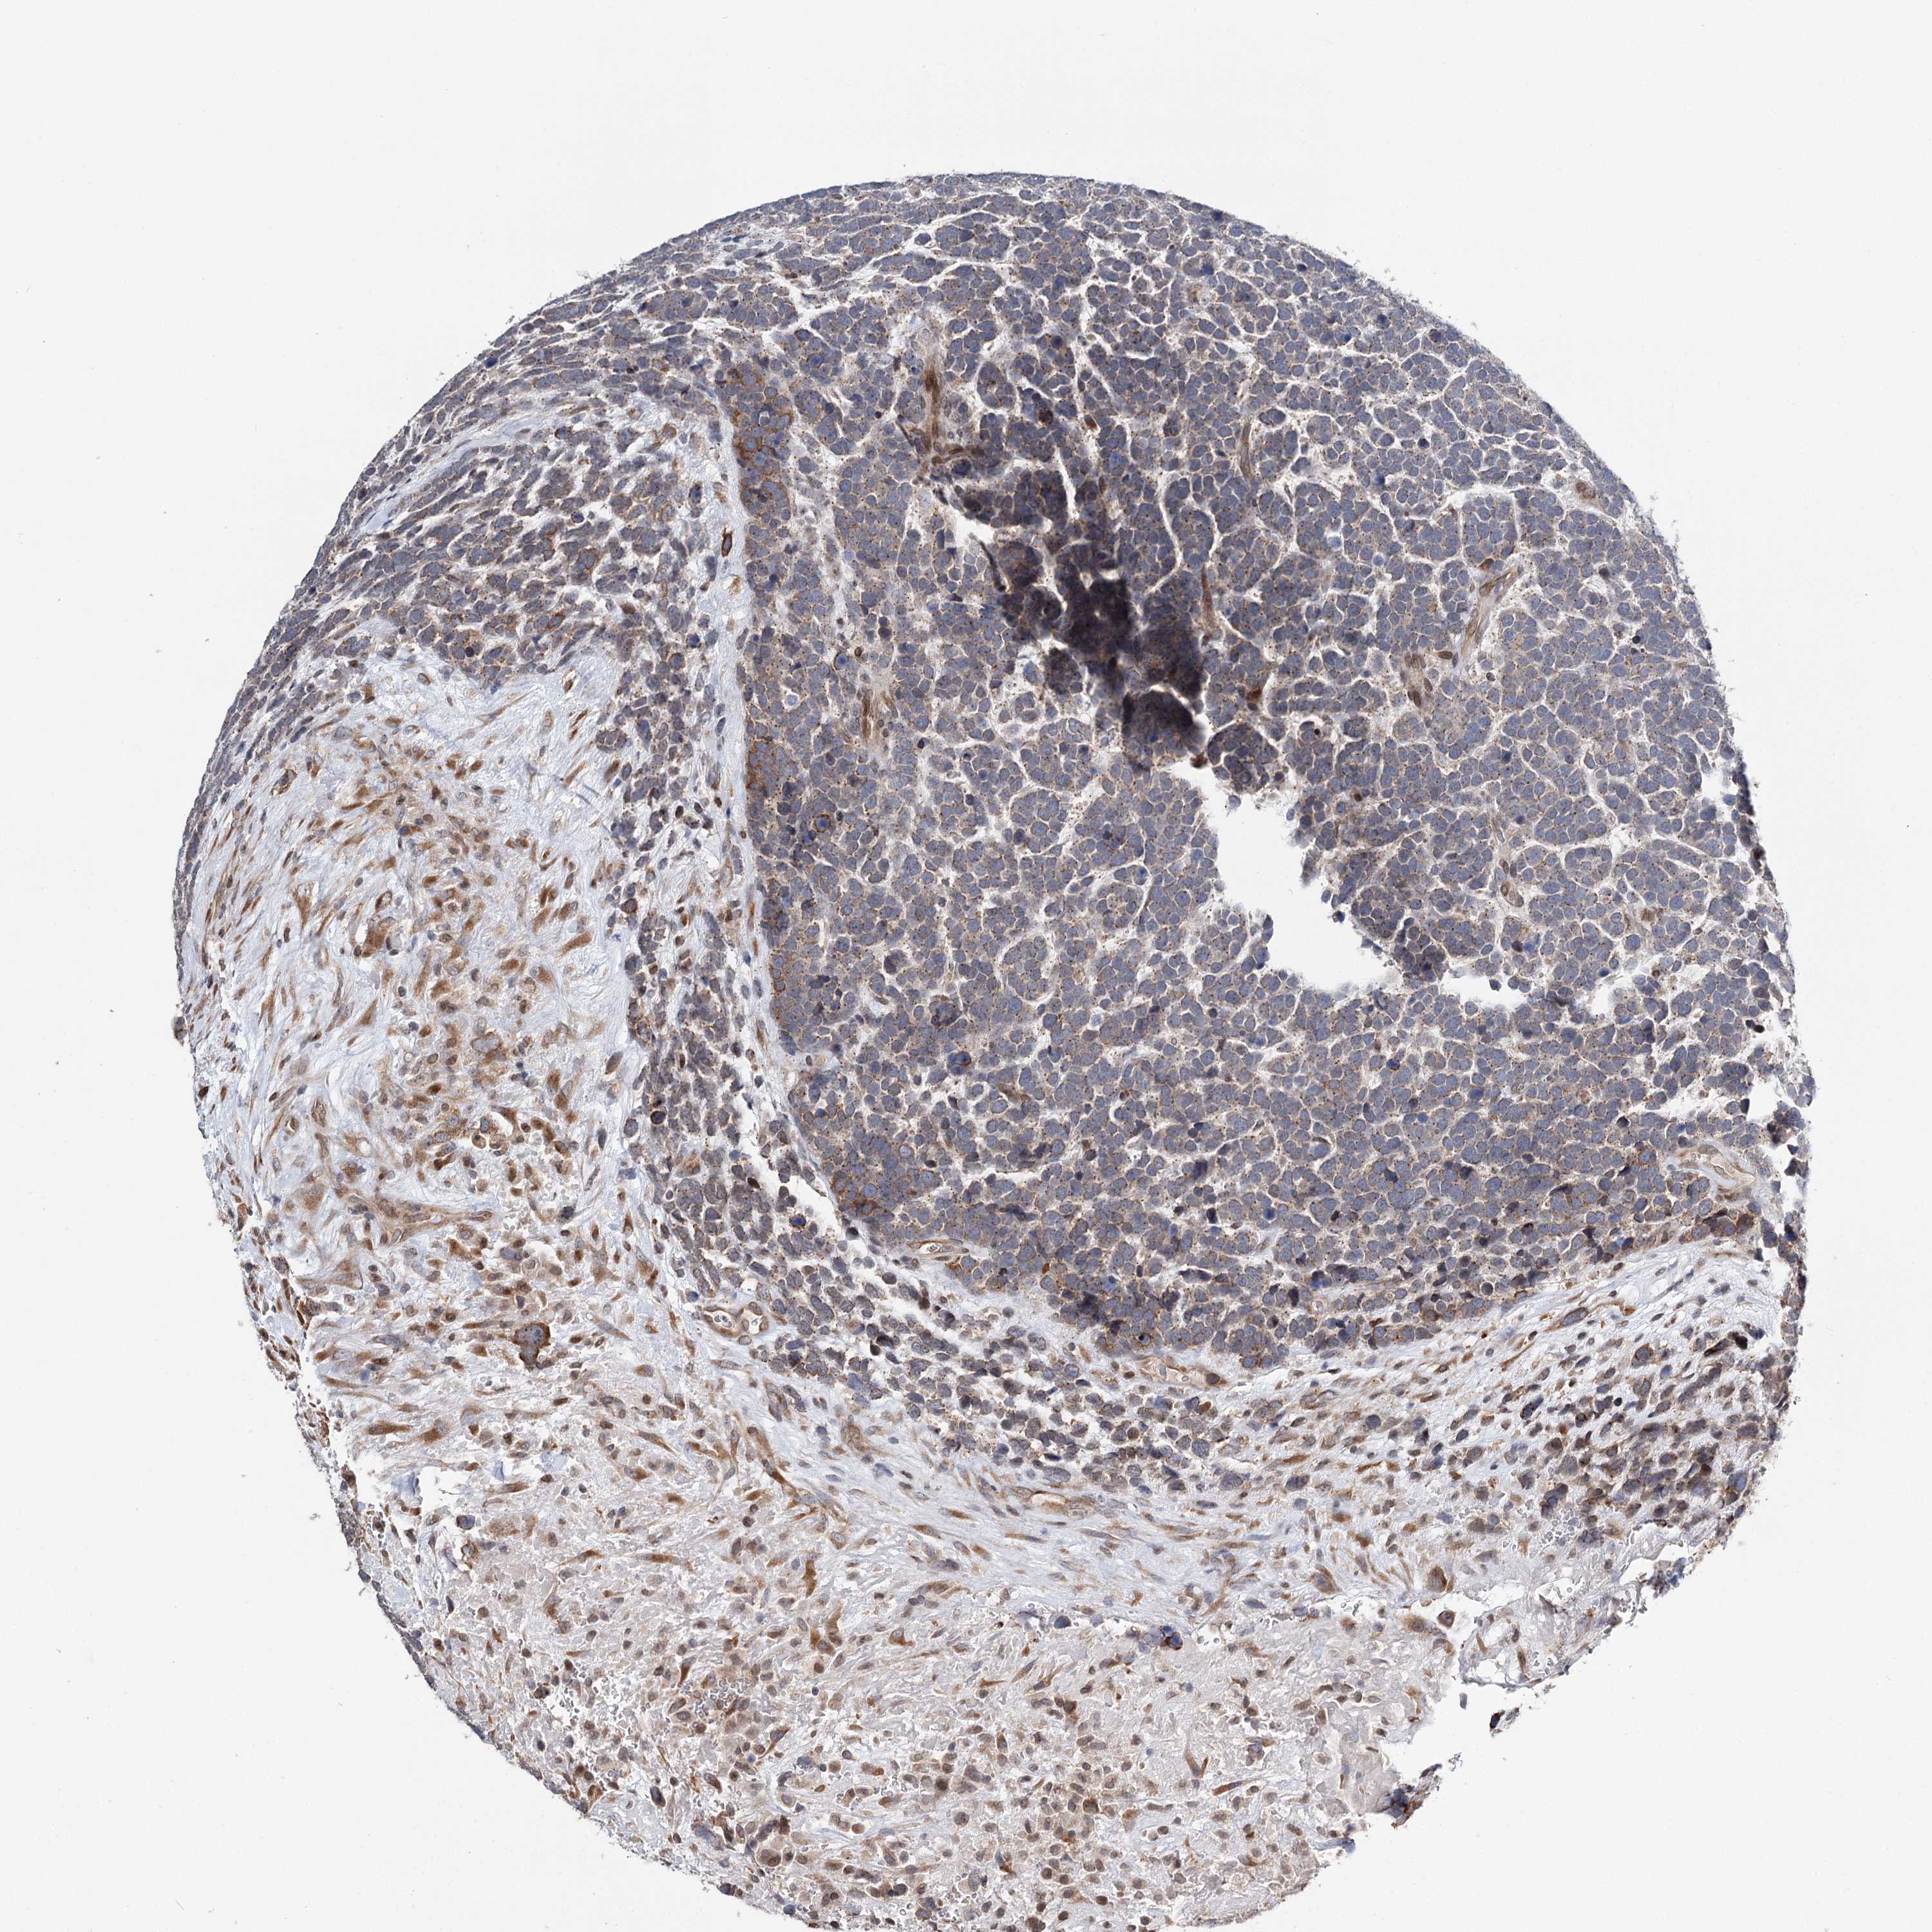

UROTHELIAL CANCER - Protein expressioni

A mouse-over function shows sample information and annotation data. Click on an image to view it in a full screen mode. Samples can be filtered based on level of antibody staining by selecting one or several of the following categories: high, medium, low and not detected. The assay and annotation is described here.

Note that samples used for immunohistochemistry by the Human Protein Atlas do not correspond to samples in the TCGA dataset.

Antibody stainingi

Antibody staining in the annotated cell types in the current human tissue is reported as not detected, low, medium, or high, based on conventional immunohistochemistry profiling in selected tissues. This score is based on the combination of the staining intensity and fraction of stained cells.

Each image is clickable and will lead to virtual microscopy that enables deeper exploration of all samples and also displays staining intensity scores, fraction scores and subcellular localization as well as patient and tissue information for each sample.

Antibody HPA037786

Antibody HPA038034

Antibody HPA038867

Antibody HPA038868

Urothelial carcinoma, High grade

Urothelial carcinoma, Low grade

Urothelial carcinoma, NOS